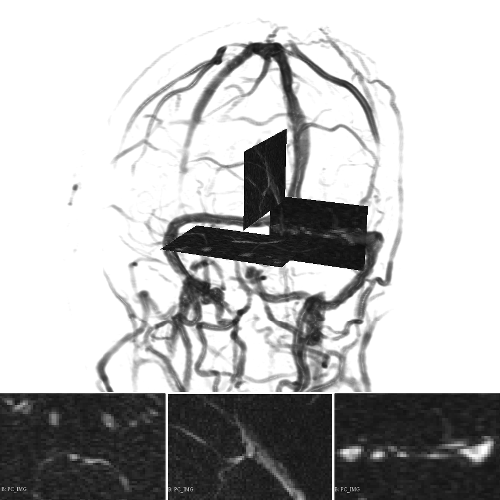

A 3D hand-crafted tortuous and convoluted phantom (HCP) is designed to account for complex vessel patterns, i.e. branching, kissing vessels, scale and shape variations induced by pathologies. Also a set of 20 synthetic vascular trees (SVT) ( voxels) were generated using VascuSynth [10] considering two levels of additional noise (N1: + Shadows: 1 + SaltPepper: ; N2: + Shadows: 1 + SaltPepper: ). Together with the synthetic data, a cerebral Phase Contrast MRI (PC) ( mm), a cerebral Time of Flight MRI (TOF) ( mm) and a carotid CTA ( mm) were used. Vascular network ground-truths (GT) are given in the form of connected raster centerlines for all the synthetic images and for both TOF and CTA.

The scalar vesselness responses of both HCP and PC images are determined using the state-of-the-art Frangi filter (FFR) [8], and Optimally Oriented Flux (OOF) [12]. Also, the connected vesselness map (CVM) and the associated tensor field (TF) are synthesized for the same dataset using VTrails. The connectedness of the considered scalar maps is qualitatively assessed and the TF is inspected as proof of concept in section 3.1.

3.1 Connectedness of the Vesselness Map

Fig. 3 shows the connectedness of vessels recovered from state-of-the-art vascular enhancers and curvilinear ridge detectors FFR and OOF together with the proposed CVM for the synthetic HCP and the real PC images.

On the synthetic phantom, FFR shows a fragmented and rough vesselness response in correspondence of irregularly shaped sections of the structure. Also, the response at the bifurcation is not smoothly connected with the branches (triangular loop). Conversely, OOF recovers the phantom connectedness at the branch-point, and the vesselness response is consistent along the tortuous curvilinear section, however ghosting artifacts are observed as the shape of the phantom becomes irregular (C-like) or differs from a cylindrical tube. Also, close convoluted structures, which change scale rapidly in the HCP, produce inconsistent responses of OOF (fig. 3). CVM shows here a strongly connected vesselness response in correspondence of both regular and irregular tubular sections, with local maxima at structures’ mid-line. The connectedness of the structures is emphasized regardless the complexity of the shape, and it resolves spatially the tortuous curvilinear ‘kissing vessels’ without additional ghosting artifacts, despite the smooth profile.

Similar results are observed on the PC dataset: FFR has a poor connected response in the noisy and low-resolution image. Vessels are overall enhanced, however thin and fragmented structures remain disconnected. Overall, the vesselness response is not uniform within the noisy structures, where maximal values are often off-centred. A more consistent response is obtained from OOF, where the connectedness of vessels is improved. Maximal response is observed at the mid-line of vessels, however, noise rejection is poor. CVM strongly enhances here the vessel connectivity. The fragmented vessels of PC have a continuous and smooth response in CVM with higher values and a more defined profile. Large vessels shows solid connected regions with local maxima at mid-line as in OOF. Conversely from OOF, CVM shows improved noise rejection in the background.

The respective tensor fields (TF) synthesized on both HCP and PC show consistent features. The TF’s characteristics are in line with the connectedness of CVM: enhanced and connected vessels are associated with high anisotropy, whereas background areas show a predominant isotropic component.